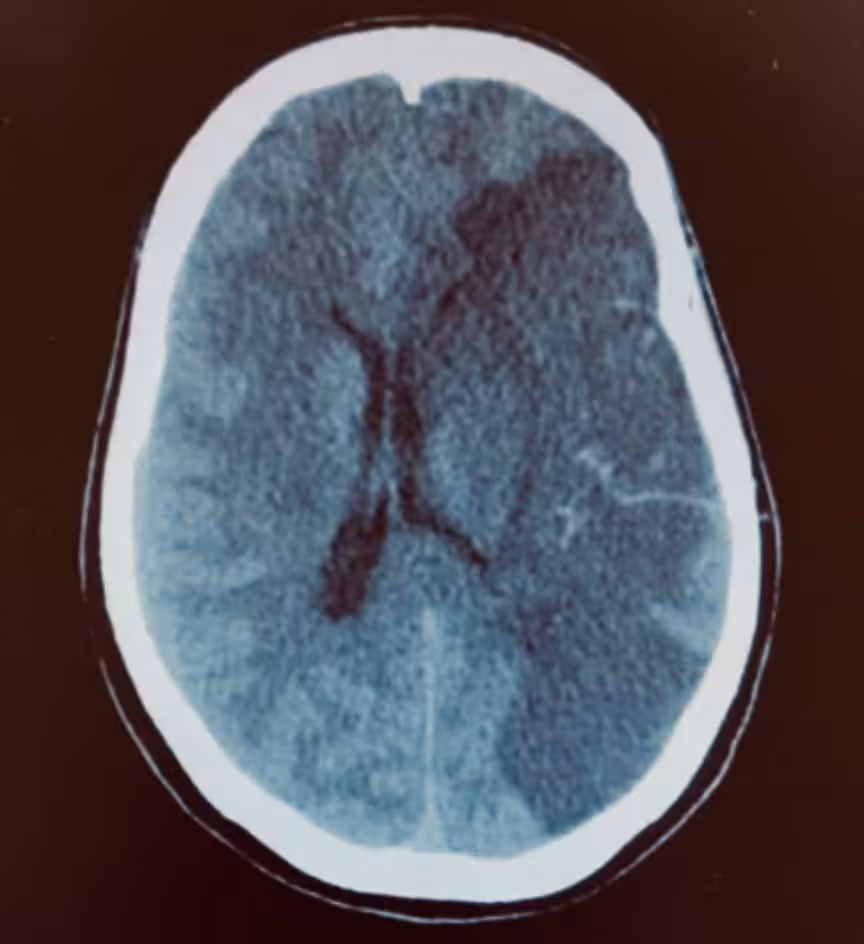

Porém, em alguns casos como o mostrado na imagem, a área de isquemia (mais escura à esquerda) é muito grande e com o desenvolvimento do edema (inchaço) no cérebro o paciente está em risco de piora das sequelas e morte. Nesses casos, chamados de AVC maligno, pode haver benefício na avaliação do Neurocirurgião. O procedimento realizado nesse caso é a craniectomia descompressiva.